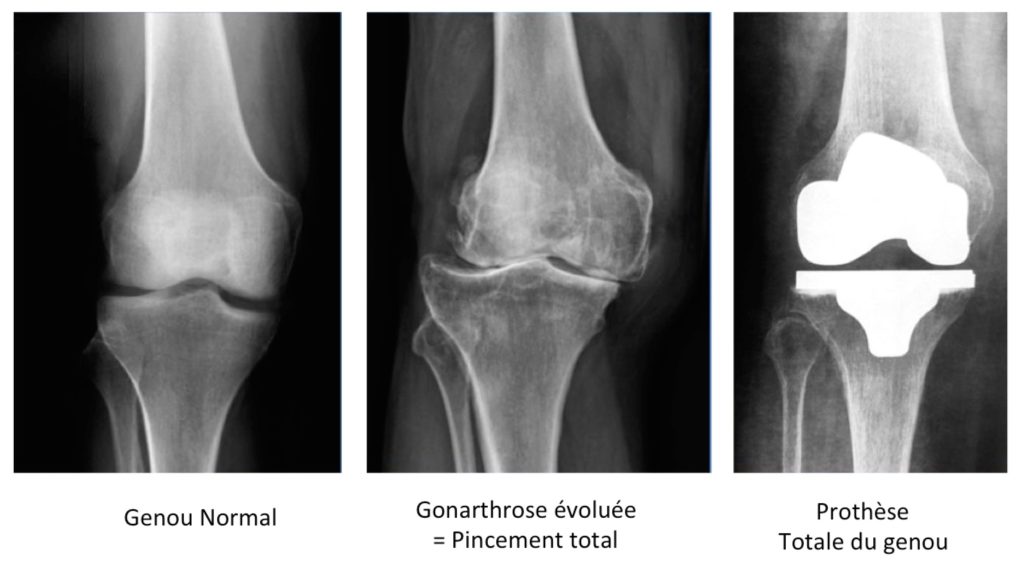

L’usure du cartilage d’une articulation est appelé « Arthrose ». Elle correspond à l’usure de ces surfaces de glissement, provoquant alors des « accrochages » et des douleurs.

Lorsque que le genou est atteint d’athrose, on parle de «gonarthrose ».

La réalisation d’une prothèse totale du genou consiste à remplacer la couche de cartilage abimée par un nouveau revêtement parfaitement lisse.

Les prothèses actuellement développées sont constituées d’un implant de surface métallique glissant sur une surface en polyéthylène (plastique rigide). Ceci redonne à l’articulation un mouvement fluide et permet de rendre au patient une liberté articulaire avec des mouvements indolores.